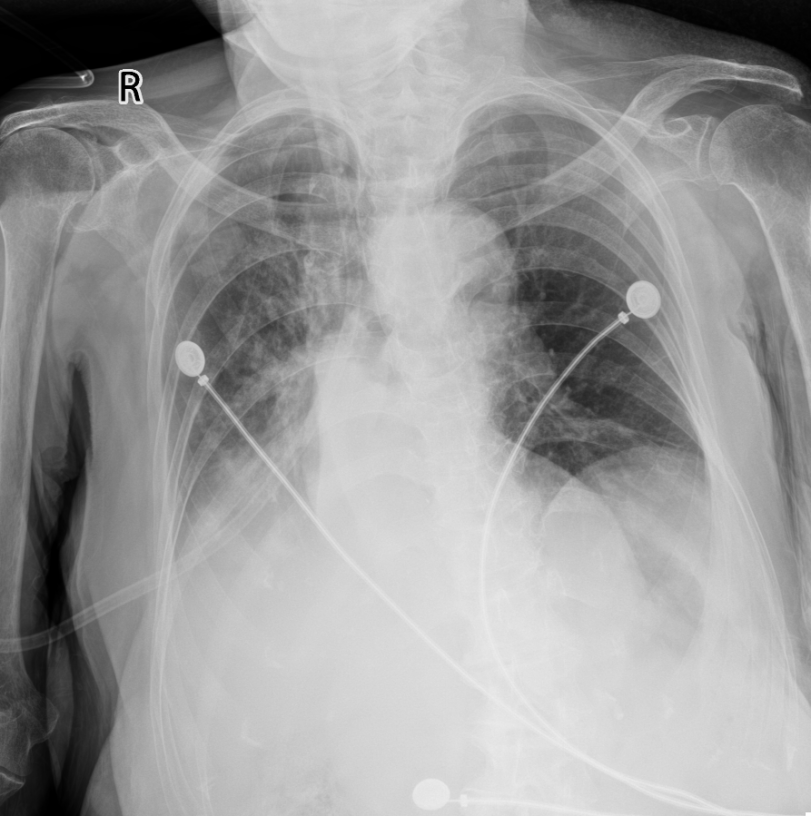

入院2025-10-28(河北省中医院)胸部正位:1.右肺门增大,右下肺密度增高,右侧膈肌及肋膈角显示不清:2.右肺多发斑片状高密度;3.心脏增大:建议CT检查。

胸部正位X线(2025-10-28河北省中医院)

挑战:长期卧床、恶病质、免疫力低下导致反复感染(双肺间质性改变、慢性支气管炎、阻塞性肺炎、呼吸衰竭),入院心率90次/分,血压98/55mmHg,血氧饱和度波动在78%-82%,外院使用头孢哌酮舒巴坦20余天无效(见图1)(白细胞仍15.07×10⁹/L,中性粒细胞84.5%)。